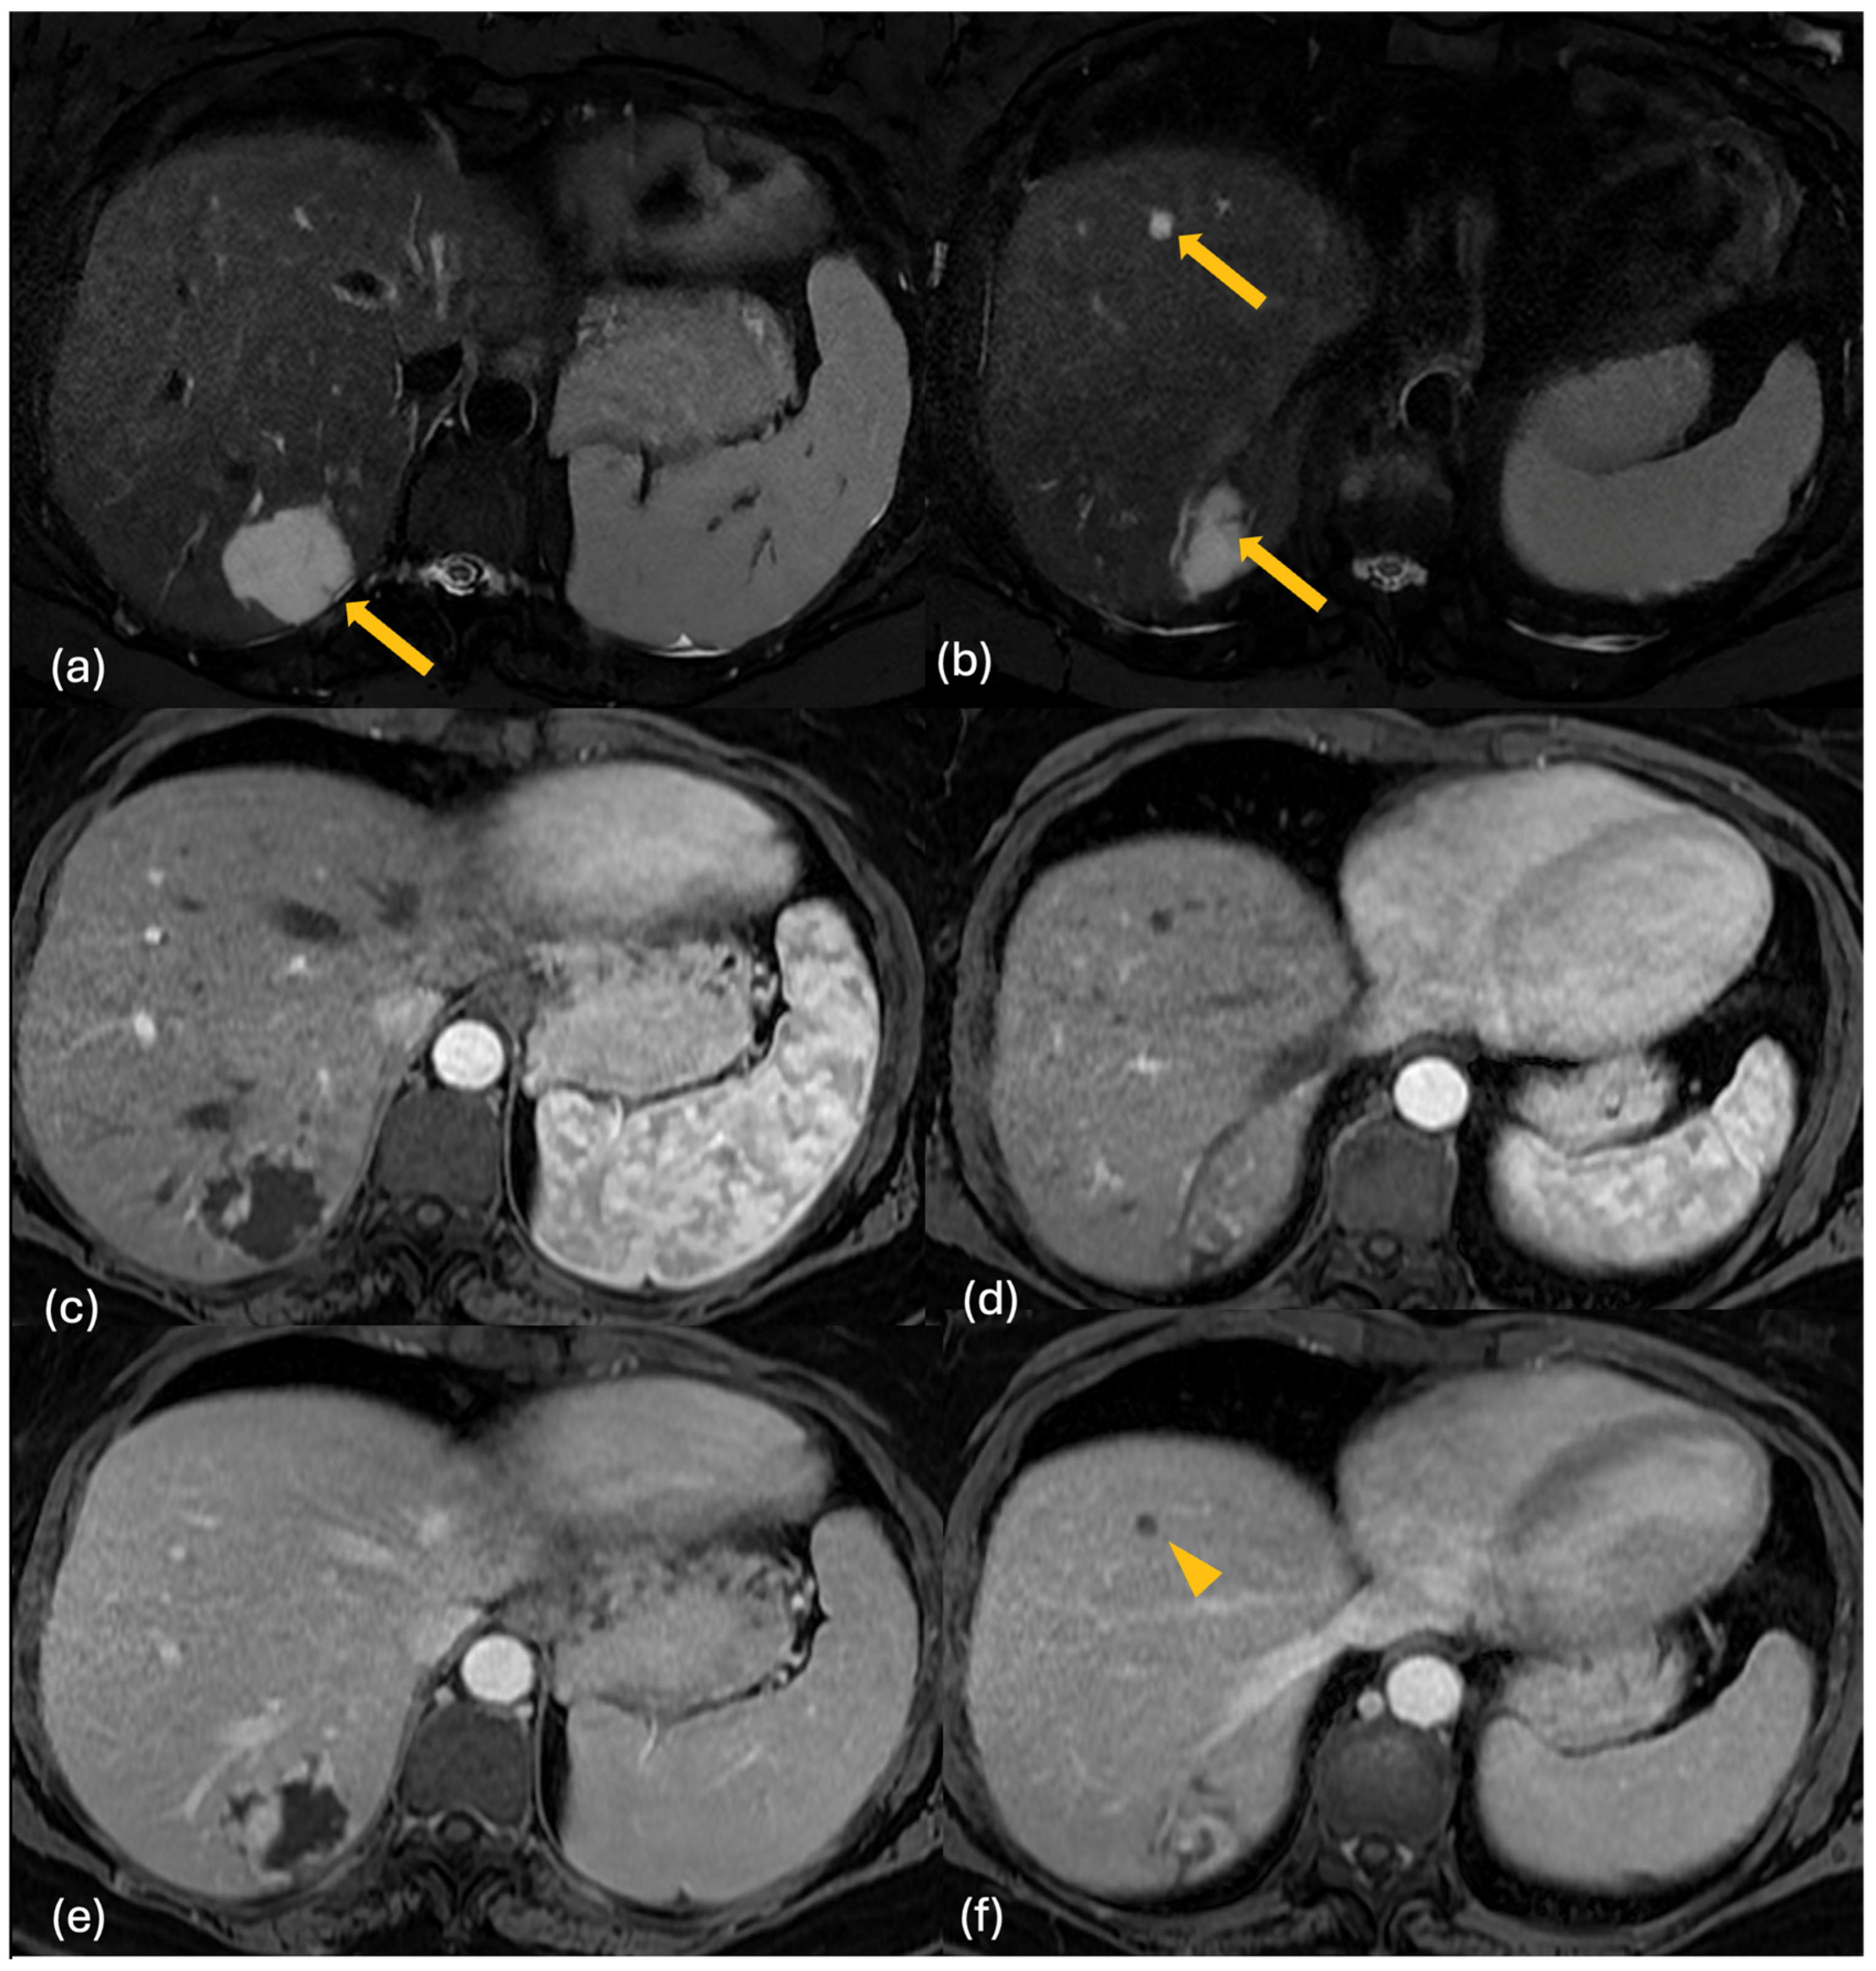

2.3. MRI